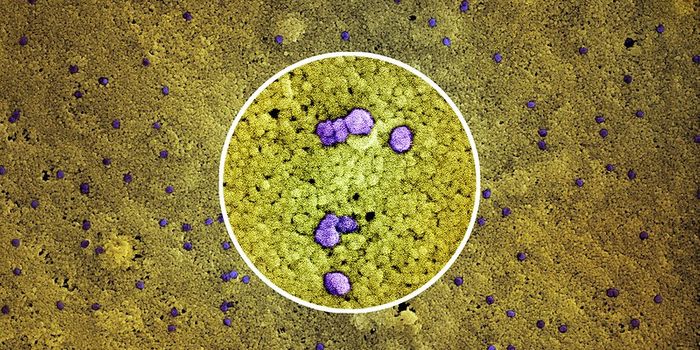

SEP 05, 2024Cell & Molecular BiologyCorynebacterium matruchotii ia a common bacterium that lives in human dental plaque; a colony is seen in this image by S ...